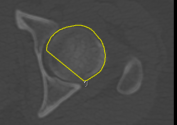

Generates a one-slice preview of the currently selected view that lets you evaluate the computed edge map and your Canny filtering and Gaussian filtering settings. Previews will appear as new items in the Data Properties and Settings panel. You can view a preview, shown below, by changing its visibility in the panel. |